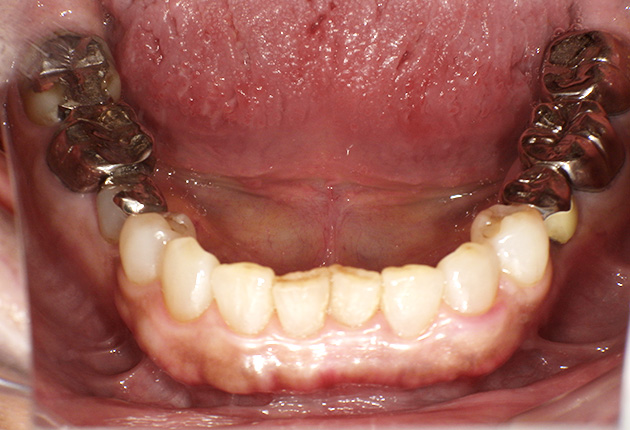

よく噛めず笑うと銀歯が目立つので気にされていました。

| 主訴 | ブリッジ脱離、しっかり噛めない |

| 診査診断 | 上顎歯牙欠損、歯周病、不良補綴、根尖性周囲炎。 不正咬合により噛み合わせのバランスが悪い事が原因により咬合治療が必要。 |

| 治療内容 | 欠損部インプラント 不正咬合に対し不良補綴のやり直しと合わせて咬合再構築 |